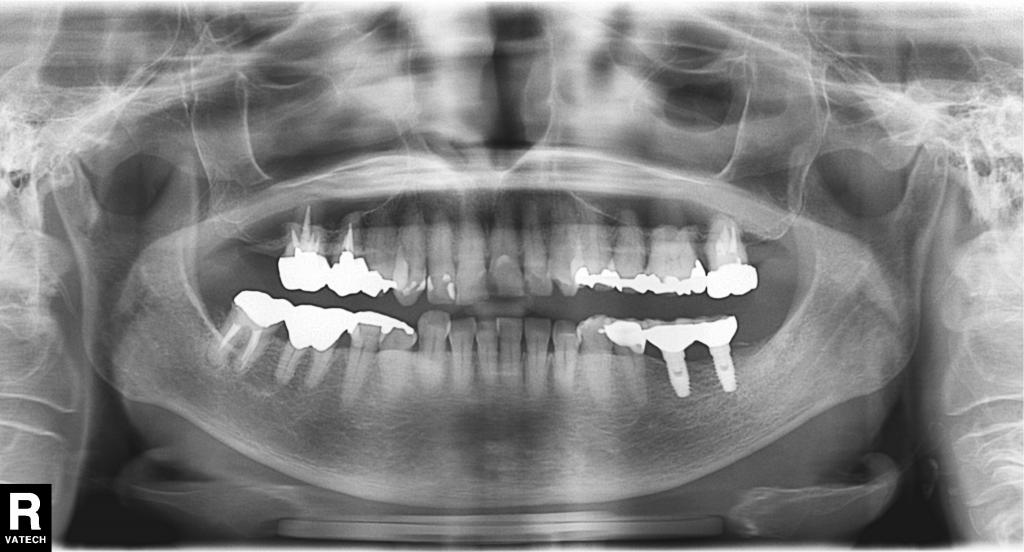

治療後写真

- 術後の全体のレントゲン写真です。

骨が大きく吸収していた部分はほぼ同じ高さに回復しています。

「骨造成」が上手くいっている状態です。